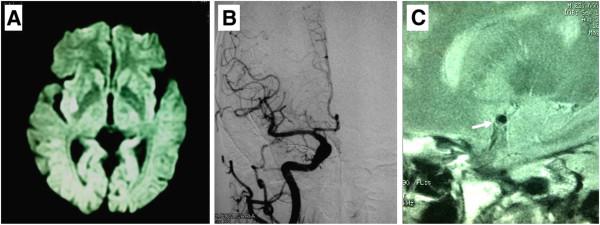

Capsular warning syndrome (CWS) is rare (1.5% of TIA presentations) but has a poor prognosis (7-day stroke risk of 60%). Up to date, the exact pathogenic mechanism of CWS has not been fully understood. We report the clinical presentations and high-resolution MRI (HR MRI) findings of two cases with capsular warning symptoms.

Case 1 was a 63-year-old man with a history of hypertension with recurrent episodes of left hemiparesis and dysarthria lasting 10 ~ 30 minutes. Case 2 was a 54-year-old woman with repetitive episodes of transient left hemiparesis and dysarthria lasting about 10 minutes. Capsular infarctions on DWI were demonstrated in the territory of a lenticulostriate artery in both 2 patients. HR MRI disclosed atherosclerotic plaques on the ventral wall of the MCA where enticulostriate arteries were arisen from, although traditional digital subtraction angiography showed normal. Aggressive medical therapy with dual antithrombotic agents and statin was effective in these two cases.

Our HR MRI data offer an insight into the pathophysiology of CWS which might be caused by atherosclerotic plaque in non-stenotic MCA wall. HR MRI might be a useful modality for characterizing atherosclerotic plaques in the MCA and detecting the pathophysiology of the CWS.

囊袋警告综合征(CWS)较为罕见(占 TIA 表现的 1.5%),但其预后较差(7 天内卒中风险为 60%)。迄今为止,CWS 的确切发病机制尚未完全阐明。我们报告了两例具有囊袋警告症状的病例的临床表现和高分辨率 MRI(HR MRI)结果。

病例 1 为 63 岁男性,有高血压病史,反复出现左侧偏瘫和构音障碍,持续 10~30 分钟。病例 2 为 54 岁女性,反复出现短暂性左侧偏瘫和构音障碍,持续约 10 分钟。两例患者 DWI 均显示壳核梗死,位于纹状体动脉供血区。尽管传统的数字减影血管造影显示正常,但 HR MRI 显示 MCA 腹侧壁存在粥样硬化斑块,纹状体动脉由此发出。这两例患者均采用双联抗血栓药物和他汀类药物进行强化治疗,效果良好。

我们的 HR MRI 数据提供了对 CWS 病理生理学的深入了解,其可能是由非狭窄性 MCA 壁中的粥样硬化斑块引起的。HR MRI 可能是一种用于表征 MCA 中粥样硬化斑块和检测 CWS 病理生理学的有用方法。